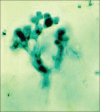

Background: Dermatophytoses refer to superficial fungal infection of keratinized tissues caused by keratinophilic dermatophytes. According to observations worldwide, dermatophytoses are the most common of the superficial fungal infections. It is common in tropics and may present in epidemic proportions in areas with high rates of humidity. Although common, the precise size of the problem defies measurement.

Conclusion: Trichophyton rubrum was the predominant species isolated (67.5%) in all clinical types followed by Trichophyton mentagrophytes. Culturing the fungus may identify the species, but it is not essential for the diagnosis as it is not a sensitive test.